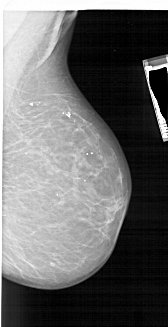

A_1866_1.RIGHT_MLO

RIGHT_MLO LINES 5881 PIXELS_PER_LINE 3016 BITS_PER_PIXEL 12 RESOLUTION 43.5 NON_OVERLAY